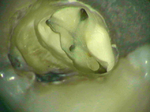

The Dental Microscope provides the dentist with unprecedented vision.

If more complicated care is required such as crowns or root canal treatment, we can provide this with improved accuracy and optimise the treatment.

The microscope has an integrated medical grade video camera so we can demonstrate live images to explain treatment decisions.